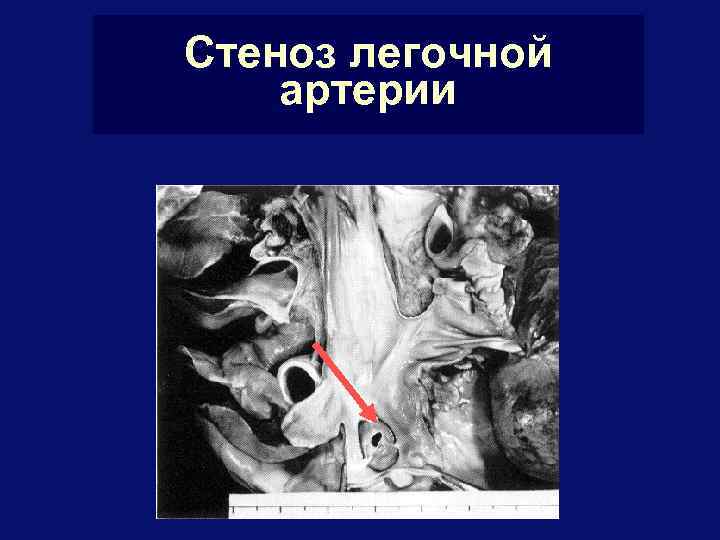

Стеноз легочной артерии

Стеноз легочной артерии

Стеноз легочной артерии - лечение § Показания к операции: с АД в Пж > 60 мм рт. § § ст. и градиент САД между Пж и Ла > 40 мм рт. ст. , ХСН II и более ФК Оптимальный возраст - старше 3 лет В настоящее время начинают лечение с РЭД У детей до 1 года – закрытая чресжелудочковая вальвулотомия, у детей старше 1 года – только открытая транслегочная вальвулопластика – рассечение комиссур под контролем зрения в условиях ИК Летальность – не более 1, 5%